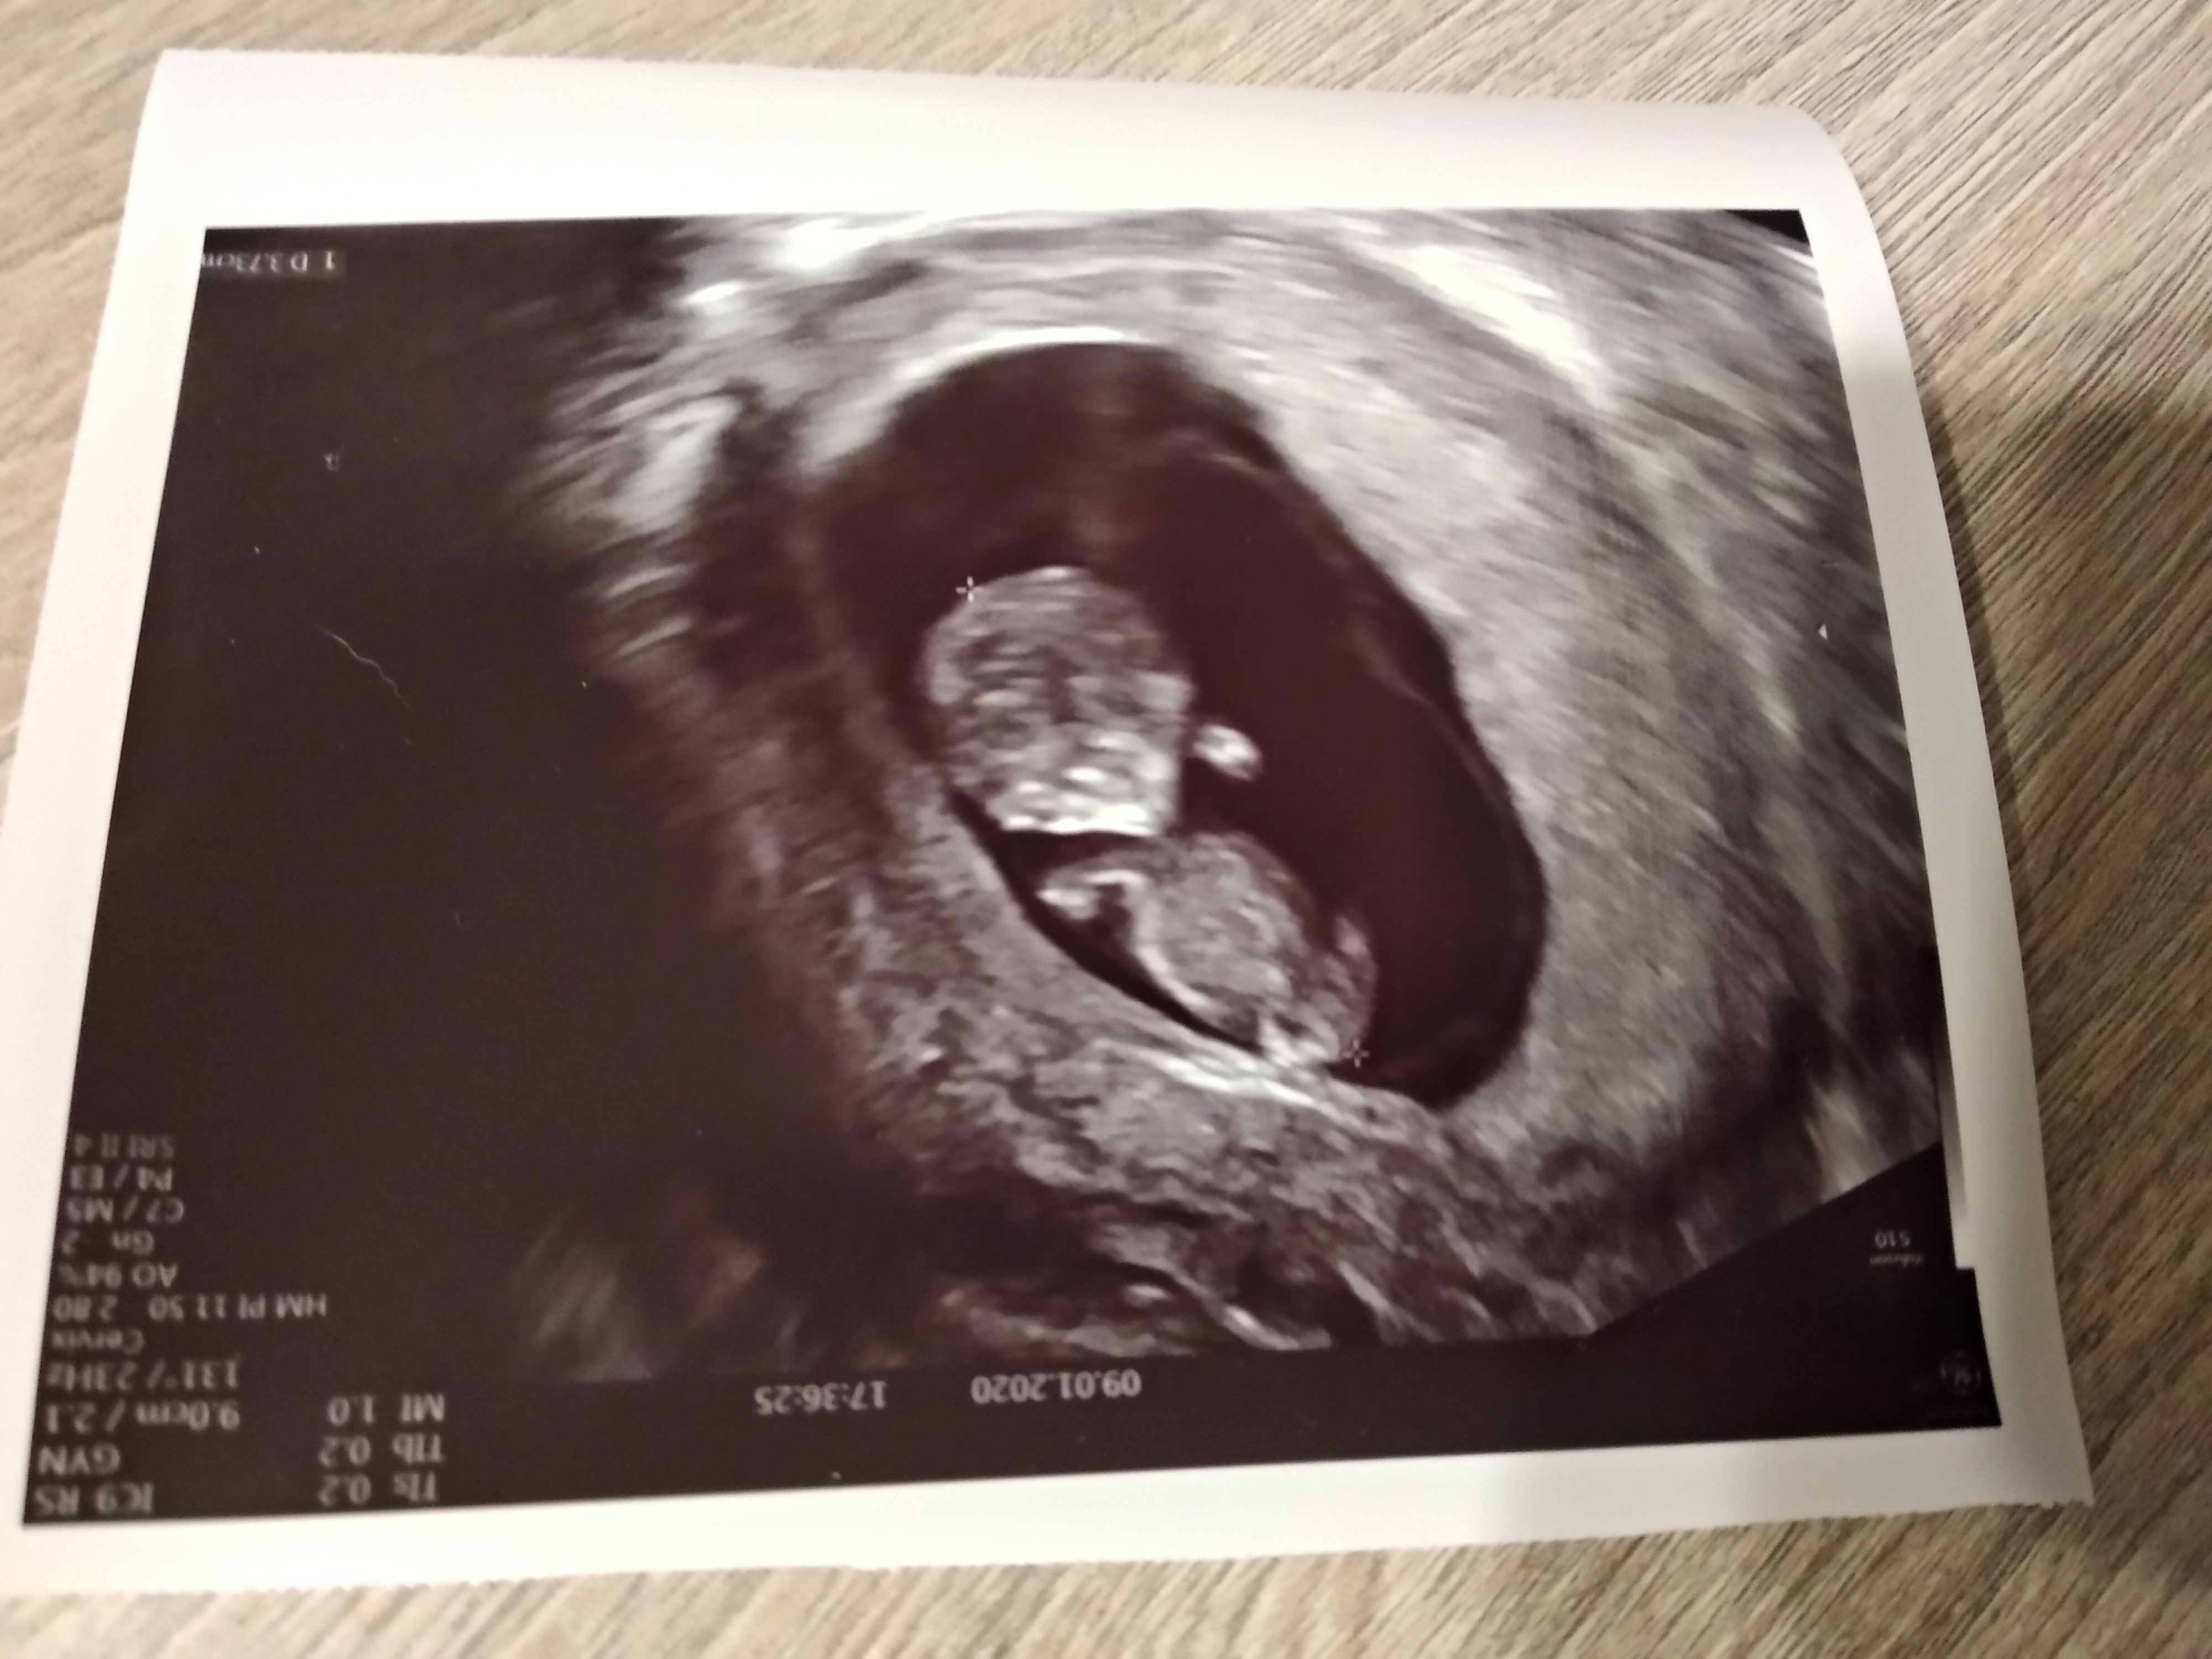

Ja już po wizycie. Wszystko wporzadku. Serducho bije, dzidzia ma już prawie 4 cm. 😍

IMG_20200109_190423_HHT.jpg